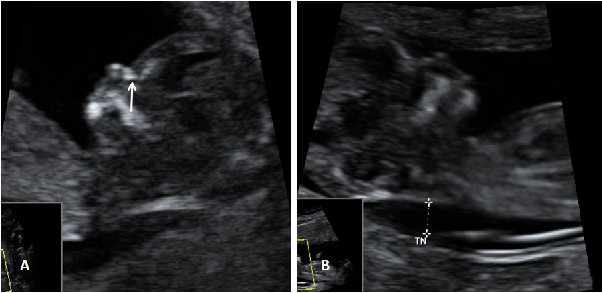

En A se aprecia el hueso nasal (flecha) en una gestación normal de 12 semanas. En B, un embrión de 12 semanas con síndrome de Down, en el que el hueso nasal está ausente y además tiene una translucencia nucal aumentada.

Imagen del hueso nasal ausente (A) y pliegue nucal aumentado (B)